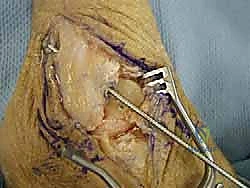

خطوات العملية الجراحية خطوة بخطوة مع الأستاذ الدكتور محمد هطيف

تتميز الجراحة في عيادة الدكتور هطيف بالدقة المتناهية واستخدام أحدث التقنيات العالمية. إليك كيف تتم العملية:

3. تجهيز الطعم (Graft Preparation):

يتم تحضير الطعم الليفي (Allograft) وتشكيله بدقة ليتناسب تماماً مع الحجم والطول المطلوبين لتعويض أربطة ATFL و CFL المفقودة.

5. تثبيت الطعم:

يتم تمرير الطعم داخل الأنفاق العظمية وتثبيته بقوة باستخدام براغي تداخلية (Interference screws) مصنوعة من مواد تذوب حيوياً وتندمج مع العظم بمرور الوقت. يتم ضبط شد الطعم بدقة لضمان ثبات الكاحل مع الحفاظ على نطاق الحركة الطبيعي.

6. الإغلاق والجبيرة:

يتم إغلاق الشقوق الجراحية الصغيرة بغرز تجميلية، ثم يوضع الكاحل في جبيرة أو حذاء طبي واقٍ لحماية الأربطة الجديدة أثناء بدء مرحلة الالتئام.